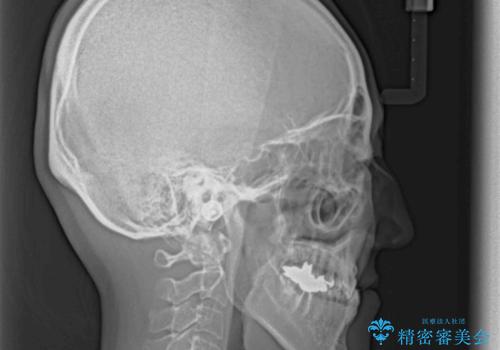

急速拡大装置 前歯の反対咬合をインビザラインで改善

- 前歯の反対咬合を気にして来院された患者様です。

上顎骨の幅が下顎骨よりも小さいので、拡大装置により骨幅を広げて上下関係を改善すると同時にワイヤー矯正で反対咬合の改善を図り、その後インビザラインにて歯並びを整えることとしました。

急速拡大装置の使用により奥歯の咬み合わせが劇的に変わり、その変化を利用して反対咬合を改善することができました。